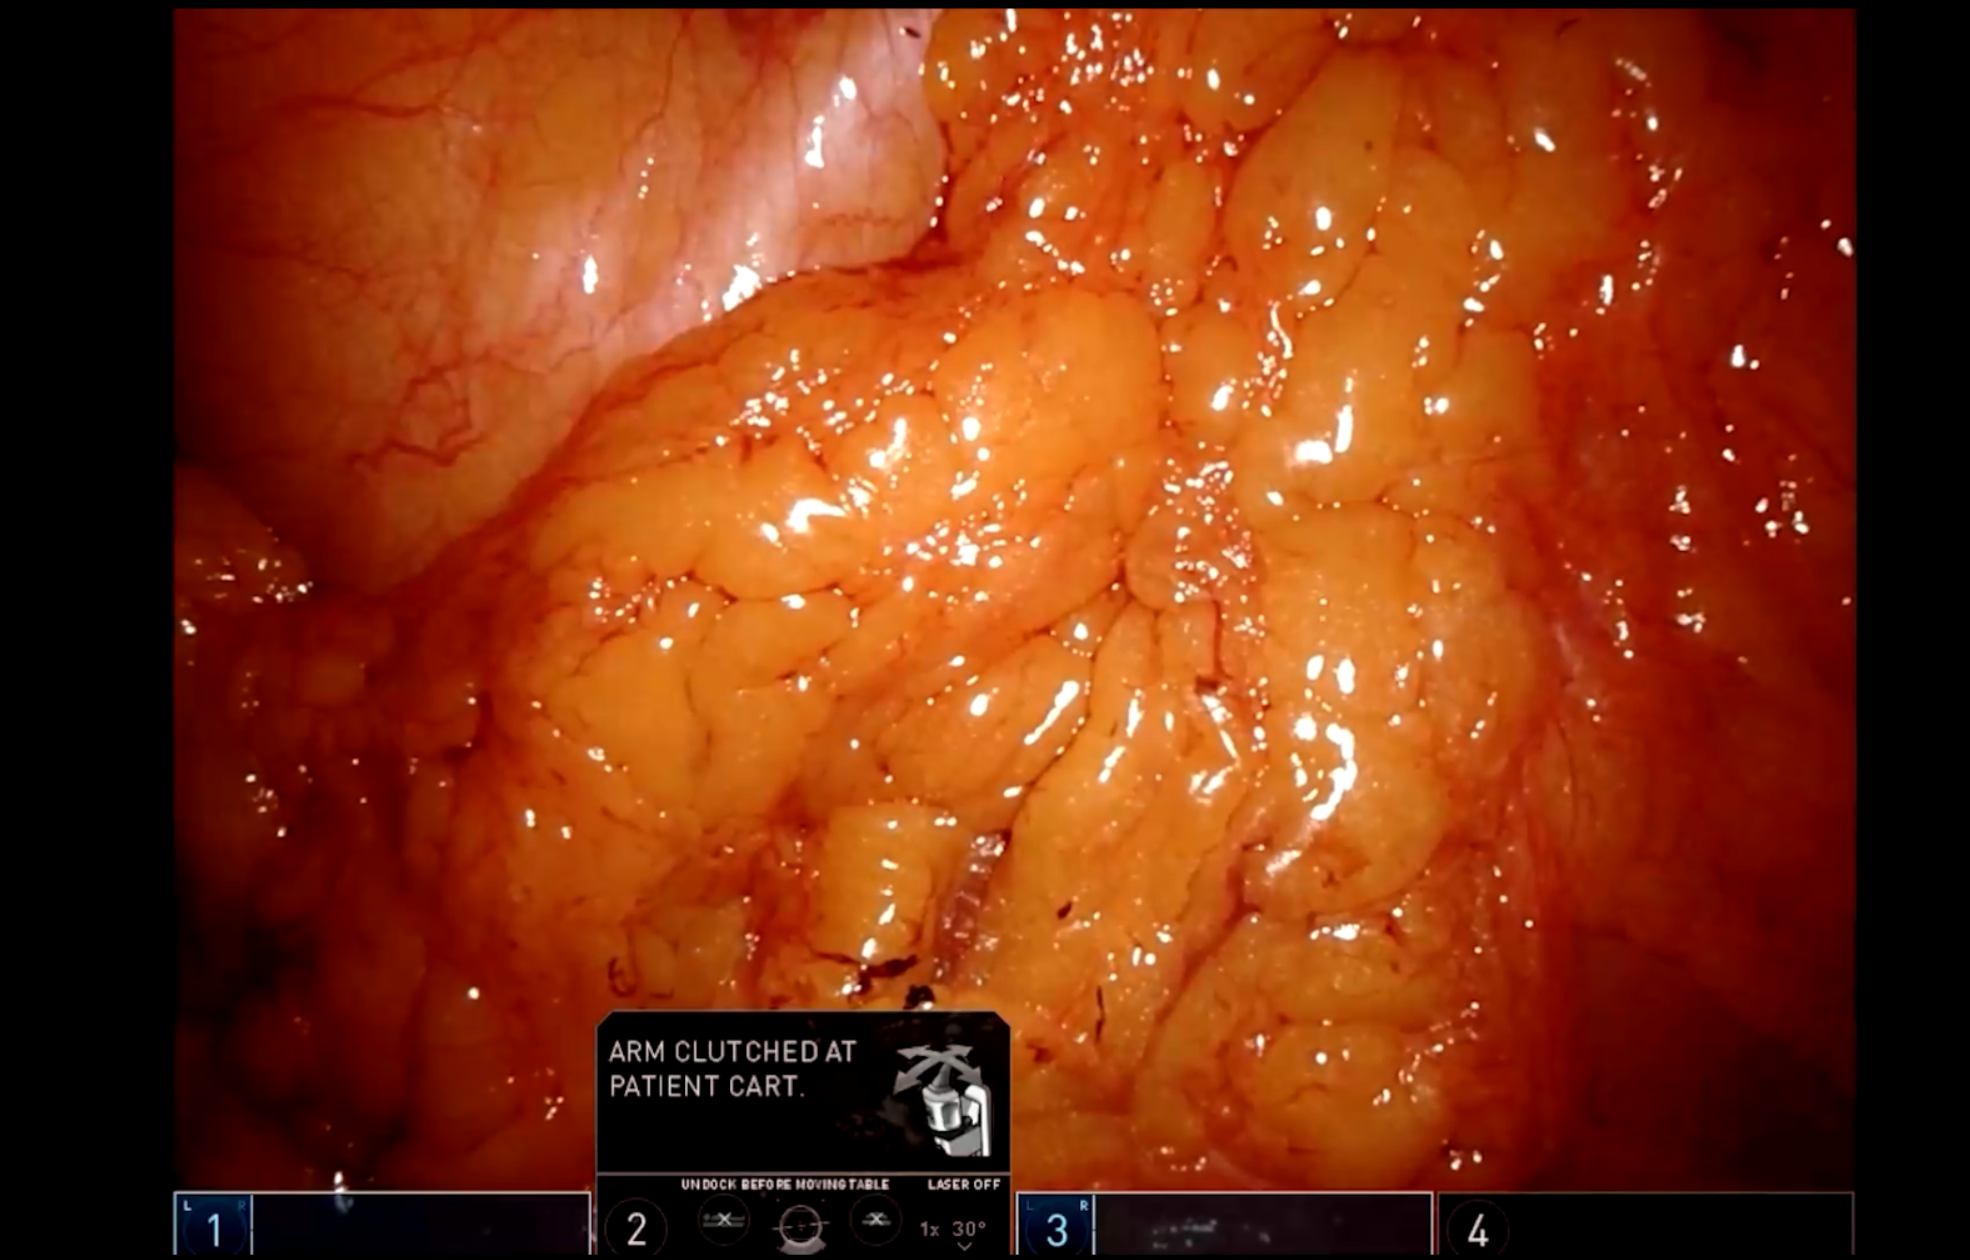

人工智能辅助技术腹腔镜下全子宫+双侧附件切除术+盆底重建术(骶前固定术)

吴桂珠教授团队